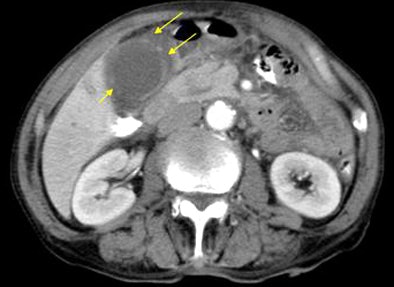

"Gallbladder rupture was seen in 16 of the 75, or about 21% of the cases," Chen said. "The most common CT findings included pericholecystic fat stranding in 71 of 75 patients, gallbladder wall enhancement, gallbladder wall thickening, and pericholecystic fluid collection."

In the analysis of CT images, "only seven findings showed significant differences between the rupture and the nonrupture group," he said. These included gallbladder wall defect (p = 0.000), intramural gas from the gallbladder (p = 0.043), intraluminal membrane of the gallbladder (p = 0.043), intraluminal gas of the gallbladder (p = 0.001), pericholecystic biloma or abscess (p = 0.009), free air (p = 0.001), and ascites (p = 0.019).

Multivariate analysis with logistic regression showed a significant association with gallbladder rupture in two findings: gallbladder wall defect (p = 0.0003, odds ratio: 30.18) and ascites (p = 0.049, odds ratio: 4.303).